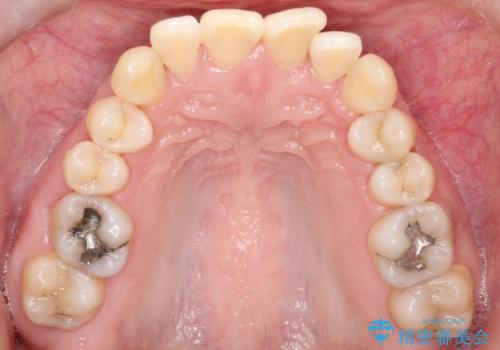

- 前歯の凸凹と前突感を改善するため、上下左右の4番を抜歯し、空いたスペースを利用して前歯を後方へ下げる審美ワイヤー矯正を計画しました。抜歯後は透明で目立ちにくい審美ブラケットを装着し、ワイヤーを用いて徐々に歯列を整えます。毎月1回の調整を通じて歯並びの変化を確認しながら、丁寧に矯正を進め、約2年で理想的な歯列と噛み合わせを完成させることを目指します。

前歯が前に出ていることや歯並びの凸凹が気になるという主訴でした。十分なスペースを確保するため上下左右の第一小臼歯(4番)を抜歯し、そこに前歯を移動させて整列を行いました。矯正装置には目立ちにくい透明なブラケットを選択し、見た目のストレスを軽減。矯正期間中は定期的な通院でワイヤーを微調整し、無理なく確実に歯を動かしました。治療後は前歯が自然な位置に下がり、口元の突出感が解消されるとともに、美しく整った口元に仕上がり、患者様にも大変喜んでいただけました。